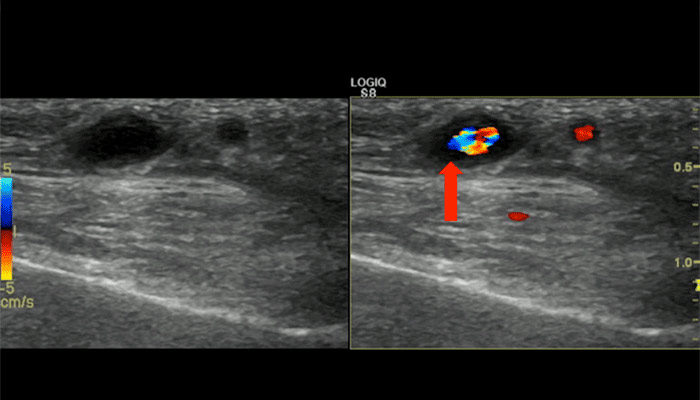

Ultrasound view of the parietal branch of the temporal artery, seen on cross-section. The dark area surrounding the blood vessel is called the “halo sign”, and indicates swelling of the wall of the vessel due to giant cell arteritis.